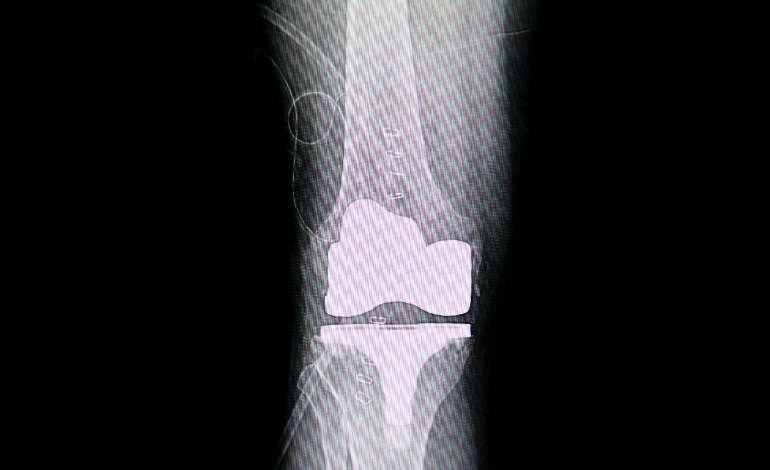

Procedimiento de Artroplastia total de rodilla en Cuernavaca e Iguala para Traumatología Y Ortopedia